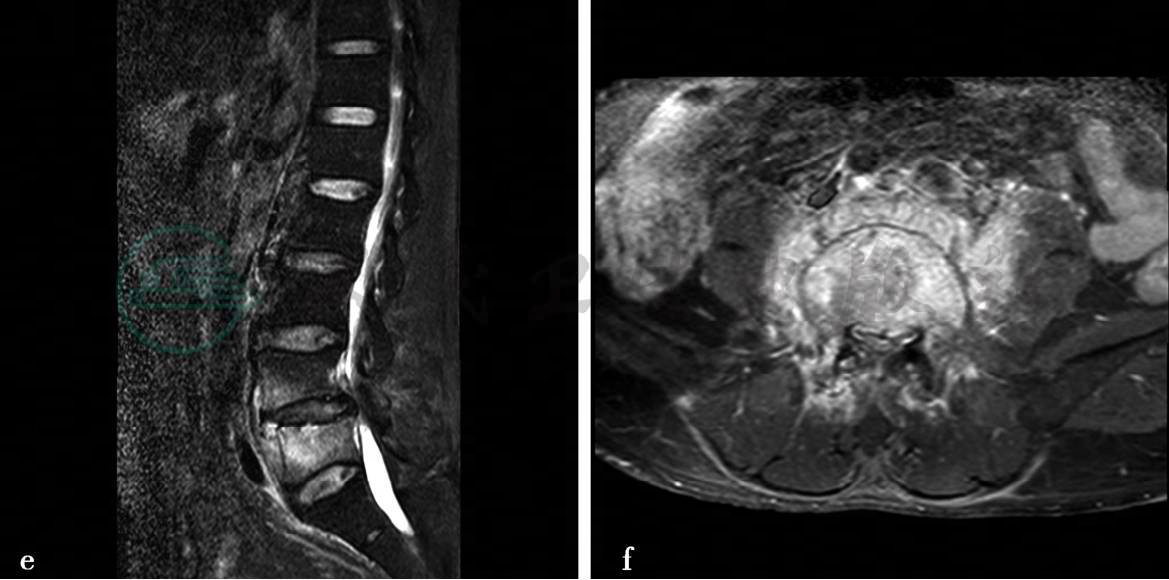

病例2:X线、CT平扫及MRI平扫、增强扫描。

图1 图1a、b,腰椎正侧位示腰椎退行性改变。图1c,腰椎CT矢状位重建(骨窗)示L5椎体骨质密度欠均匀,L4-5椎旁可见软组织密度影。图1d,腰椎MRI平扫示T1WI。图1e,T2WI示L4、L5椎体呈长T1长T2信号,L4/5椎间盘信号略减低,椎体周围可见长T1长T2信号环绕,与两侧腰大肌分解不清。图1f,腰椎MRI轴位增强图像示病变椎体及周围异常信号影明显强化